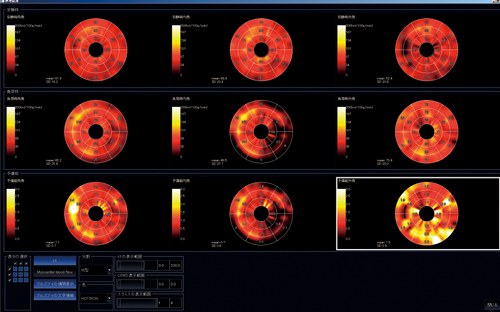

“心筋パフュージョン”は,心筋血流量を定量評価するソフトウェアである。従来の心筋パフュージョンMRIでは視覚評価法や半定量評価法のup-slope法などいくつかの問題点が指摘されてきたが,これはAZE社と三重大学などが,その克服のために共同開発したソフトウェアである。

この定量方法は,左心室の血液入力カーブと心筋出力カーブに対して2コンパートメントモデルに基づいたパトラック解析を行い,心筋血流の定量値を算出するというものである。

撮像は,従来の心筋負荷時と安静時の撮像に加えて,同条件にて10倍希釈造影剤による補正データを撮像する。3つの撮像データをすべて読み込み,スライス,フェーズそれぞれにおいて心外膜・心内膜・血液領域のROIをトレースする(図4)。ROIのトレースが終わると,定量解析結果が安静時・負荷時・予備能がBull’s eye表示される(図5)。スライス数で見ると非常に多い枚数のトレースの確認と修正を必要とするが,修正も簡便に行えるようになっており,比較的覚えやすく,慣れやすい処理であると感じている。

図4 ROIのトレース画面

図5 心筋パフュージョン解析結果